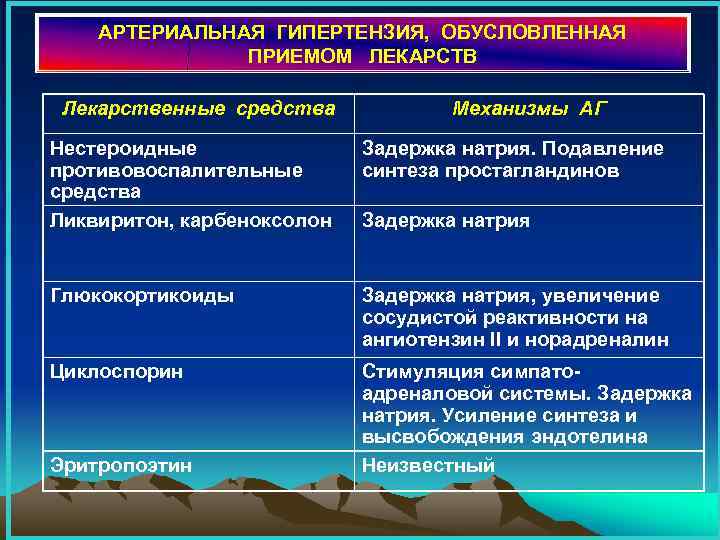

АРТЕРИАЛЬНАЯ ГИПЕРТЕНЗИЯ, ОБУСЛОВЛЕННАЯ ПРИЕМОМ ЛЕКАРСТВ Лекарственные средства Механизмы АГ Ингибиторы моноаминооксидазы Стимуляция симпатоадреналовой системы Симпатомиметики: капли в нос; бронхолитики; катехоламины Трициклические антидепрессанты (имипрамин и др. ) Стимуляция симпатоадреналовой системы Тиреоидные гормоны Таблетированные контрацептивы Стимуляция симпатоадреналовой системы. Ингибирование обратного захвата норадреналина нейронами Эффект тироксина Задержка натрия. Стимуляция ренинангиотензиновой системы

АРТЕРИАЛЬНАЯ ГИПЕРТЕНЗИЯ, ОБУСЛОВЛЕННАЯ ПРИЕМОМ ЛЕКАРСТВ Лекарственные средства Механизмы АГ Ингибиторы моноаминооксидазы Стимуляция симпатоадреналовой системы Симпатомиметики: капли в нос; бронхолитики; катехоламины Трициклические антидепрессанты (имипрамин и др. ) Стимуляция симпатоадреналовой системы Тиреоидные гормоны Таблетированные контрацептивы Стимуляция симпатоадреналовой системы. Ингибирование обратного захвата норадреналина нейронами Эффект тироксина Задержка натрия. Стимуляция ренинангиотензиновой системы

АРТЕРИАЛЬНАЯ ГИПЕРТЕНЗИЯ, ОБУСЛОВЛЕННАЯ ПРИЕМОМ ЛЕКАРСТВ Лекарственные средства Механизмы АГ Нестероидные противовоспалительные средства Ликвиритон, карбеноксолон Задержка натрия. Подавление синтеза простагландинов Глюкокортикоиды Задержка натрия, увеличение сосудистой реактивности на ангиотензин II и норадреналин Циклоспорин Стимуляция симпатоадреналовой системы. Задержка натрия. Усиление синтеза и высвобождения эндотелина Неизвестный Эритропоэтин Задержка натрия

АРТЕРИАЛЬНАЯ ГИПЕРТЕНЗИЯ, ОБУСЛОВЛЕННАЯ ПРИЕМОМ ЛЕКАРСТВ Лекарственные средства Механизмы АГ Нестероидные противовоспалительные средства Ликвиритон, карбеноксолон Задержка натрия. Подавление синтеза простагландинов Глюкокортикоиды Задержка натрия, увеличение сосудистой реактивности на ангиотензин II и норадреналин Циклоспорин Стимуляция симпатоадреналовой системы. Задержка натрия. Усиление синтеза и высвобождения эндотелина Неизвестный Эритропоэтин Задержка натрия